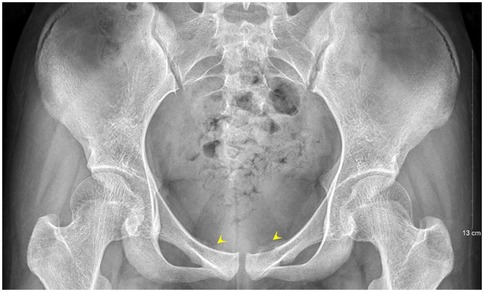

Figure 8

Figure 8. Follow-up pelvic radiograph at 22 weeks postoperatively shows callus formation at the bilateral pubic rami.